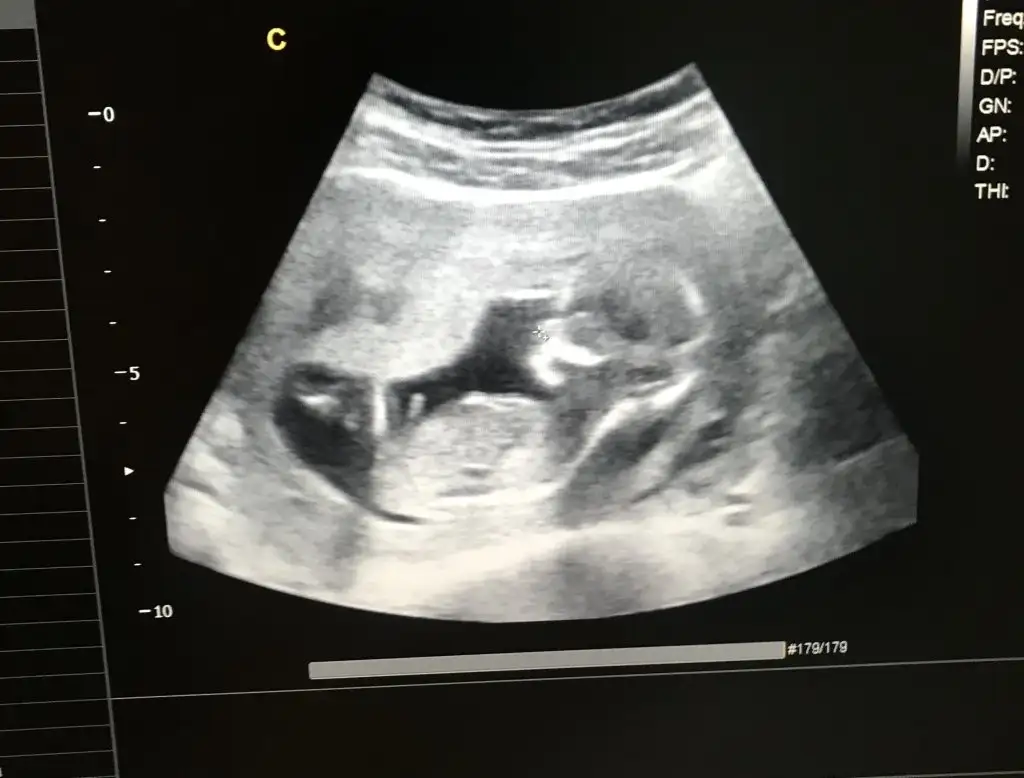

Cinsiyettt tahmini🥰❤️lütfennnnn

13 haftalik ti benim kemik yapisindan kıza benziyor dedi cin takvimi erkek yazıyor kemik yapisinda belli oluyor mu ya cinsiyet

Evet kemik yapisindan anliyor doktorlar. Kiza benziyor dediyse yuzde 89,90 kizdir. Ben de 11 haftalikken doktorum 2 hafta onden gidiyordu kizim, kesinlikle kiz dedi. Yanilmadi da, kemik yapisindan anliyorlar